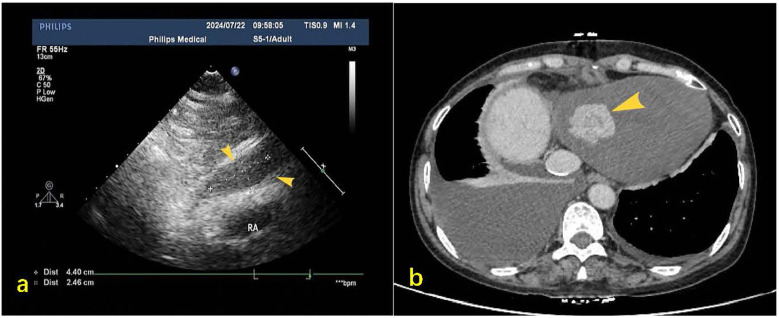

Cardiac tumors constitute an exceptionally rare neoplastic entity posing significant diagnostic challenges. We report a 55-year-old female patient without prior oncologic history who presented with acute-onset bilateral lower extremity edema progressing over 72 h. Transthoracic echocardiography demonstrated a pericardial mass with concomitant hemorrhagic pericardial effusion. Subsequent magnetic resonance imaging and systemic positron emission tomography localized the lesion to the right bottom of the heart. Surgical exploration suggested a cardiac occupancy as an irregular, fish-flesh-like soft tissue mass, pathology biopsy was performed suggesting a malignant tumour of epithelial origin, and immunohistochemistry was suggestive of hepatic origin. The patient received combination therapy comprising programmed death-1 inhibitor camrelizumab (200 mg via intravenous infusion every 21 days) and oral lenvatinib (8 mg once daily). Serial contrast-enhanced computed tomography of the thorax and abdomen demonstrated progressive metastatic dissemination with malignant pleural and peritoneal effusion formation. Despite therapeutic intervention, the patient ultimately experienced disease progression culminating in mortality.